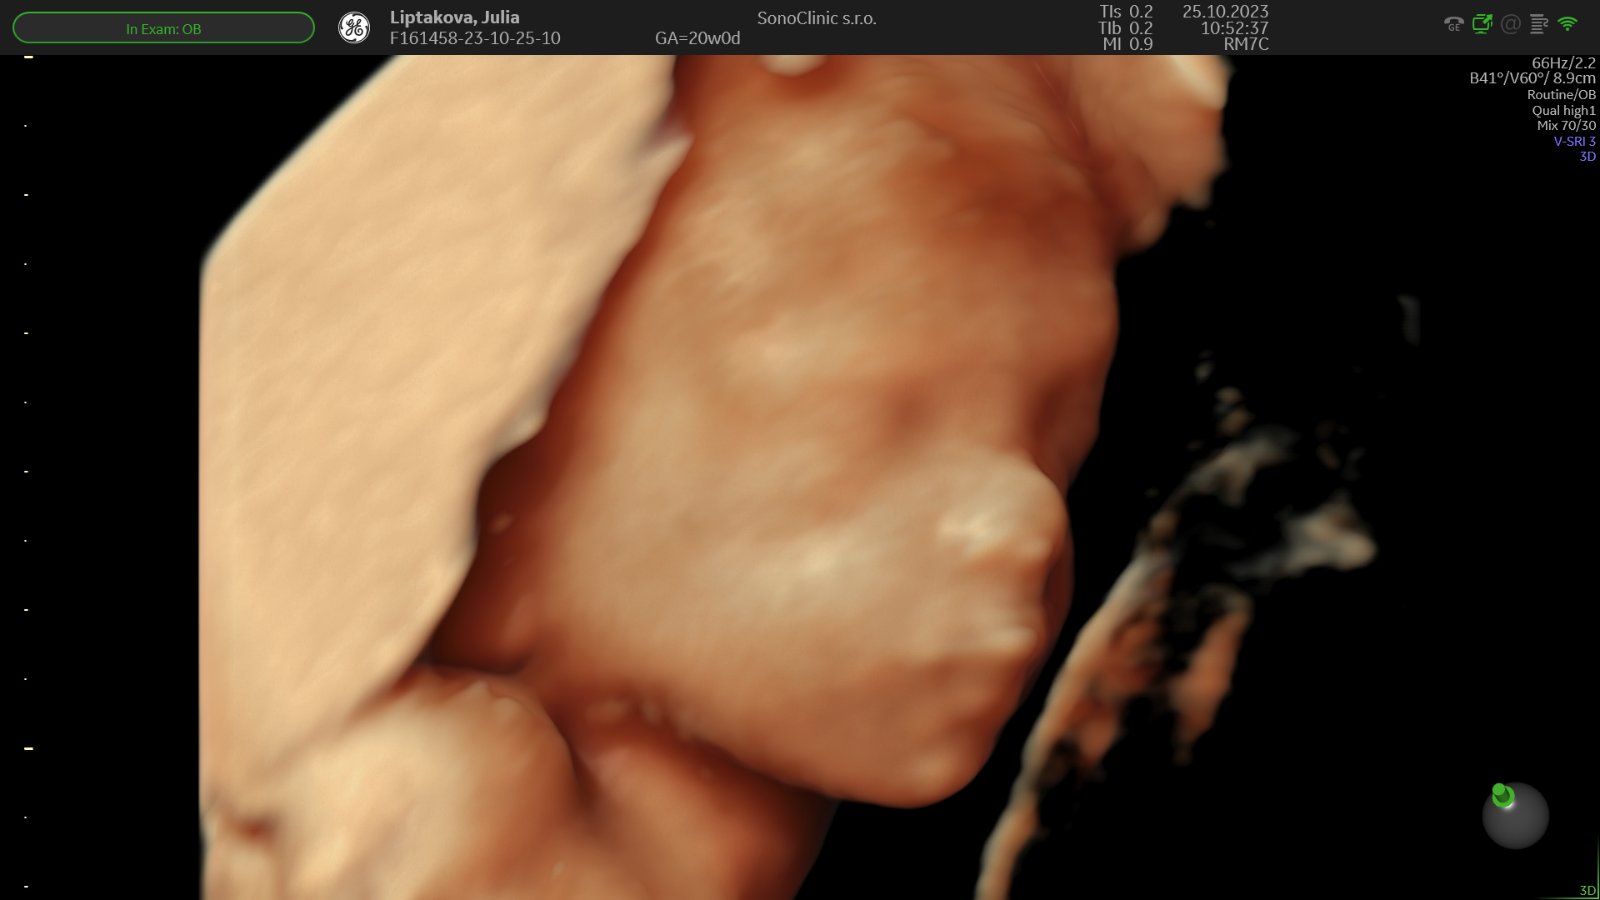

@lechmanova super, tesim sa s tebou, ze vsetko v poriadku. Aj ti urobili nejake pekne foto 3D tvaricky? Tiez by som na genetiku nesla..

@lechmanova to som dostala na usb, aj videa ako sa malý smeje a cmula si palec 🙈 a potom už len organy..

@jujulip váš malý cmúlal palček a náš počítal palce po jednom si ich vyrovnával 😁 zlaté to bolo